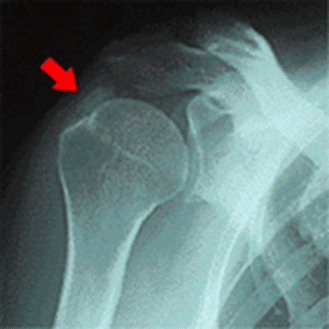

レントゲンを撮ると肩の部分に白く小さい塊が映っていることがあり、これが石灰です。

この石灰が周囲の筋肉等の組織に炎症を起こし、肩の痛みを強くしています。